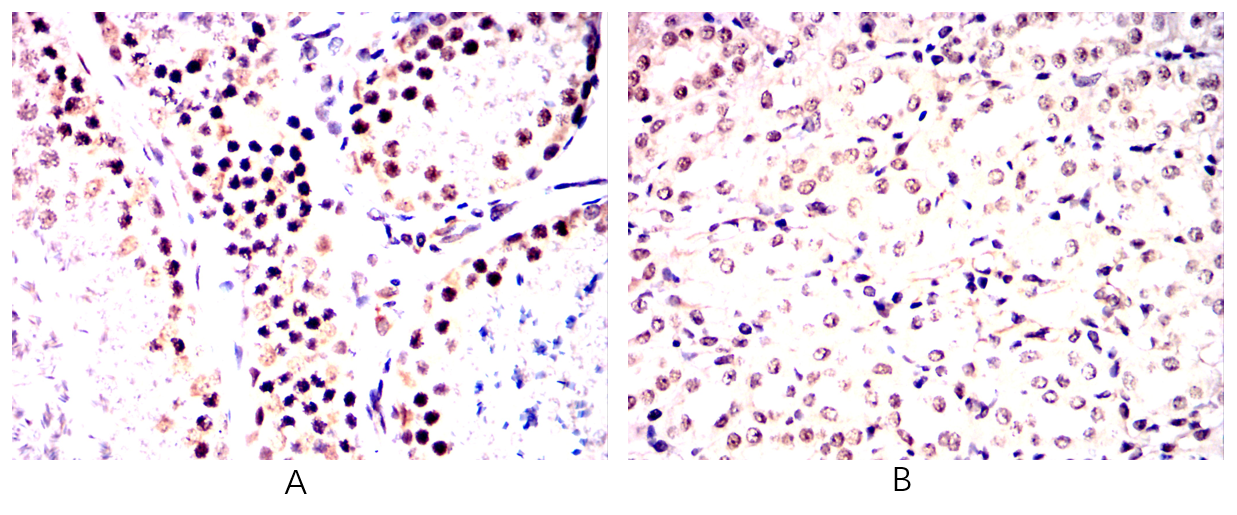

Immunohistochemical analysis of paraffin-embedded Rabbit testis(A)Rabbit kidney(B) using ISL1 mouse mAb with DAB staining.